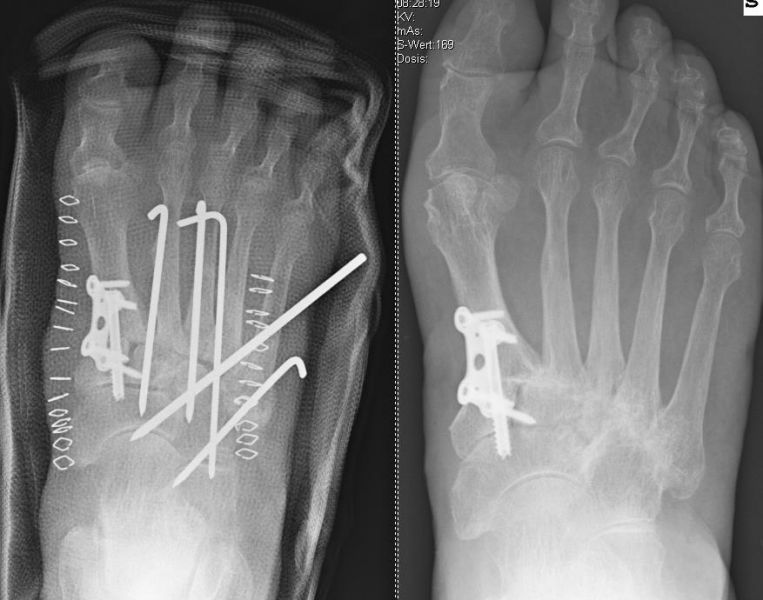

Es kommen verschiedene technische Möglichkeiten der operativen Versorgung in Frage.  Verwendung finden vor allem winkelstabile Plattensysteme, Schraubenosteosynthesen, Klammern, intraossäre Nagelsysteme, temporäre Kirschnerdraht-Transfixationen, Einbolzen von trikortikalem Span und Anlagerung von Spongiosa aus dem Beckenkamm oder dem Tibiakopf  (Abb. 2 und 3).

Die isolierte Arthrose der Bona Jäger Gelenkreihe (navikulocuneiforme Gelenk) ist selten und oft posttraumatisch. Meistens geht die navikulocuneiforme Arthrose mit einem schmerzhaften Pes planovalgus einher 2425. Letztlich werden die betroffenen Gelenkflächen angefrischt und mittels verschiedener Implantat-Möglichkeiten (s.o.) fusioniert. Bei gleichzeitiger Plattfußfehlstellung sollte diese ebenfalls adressiert werden 26 (Abb. 4). Ziel ist die Arthrodese in anatomischer Stellung der Gelenke.

Die Operation erfolgt meist über einen medialen Zugang. Nach Entknorpeln der  Gelenkflächen und Anfrischen des subchondralen Knochens kann die Arthrodese mit Schrauben oder Plattensystem erfolgen (Abb. 5). Bei Fehlstellungen muss diese vor der Osteosynthese korrigiert und das Talonavikulargelenk reponiert werden. Pseuarthrosen werden hier zwischen 8-25% angegeben 3223.